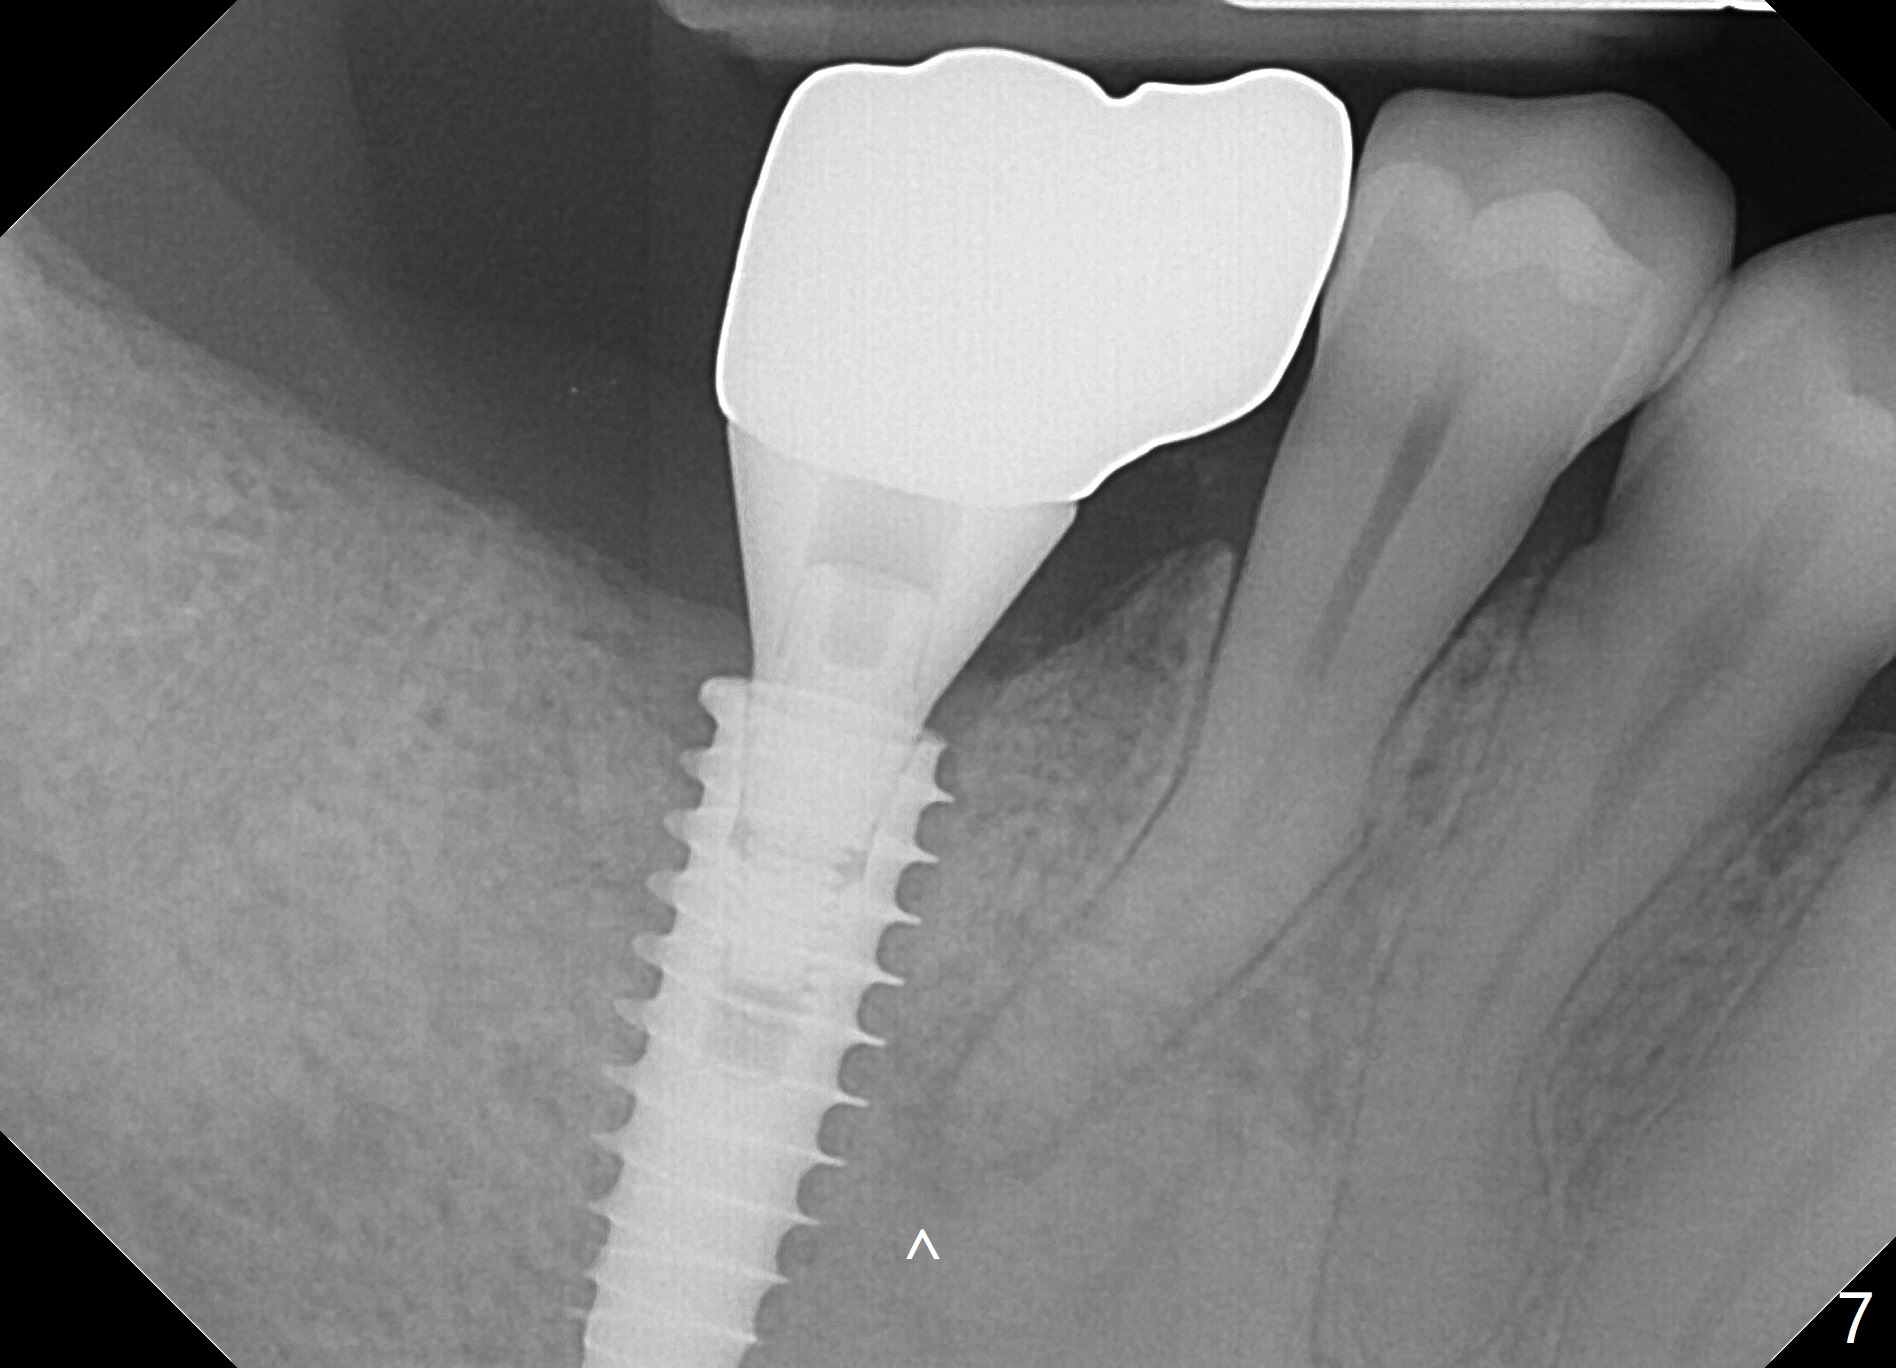

Bone graft seems to sink down and becomes denser 3 months postop (Fig.6 arrow). The bone continues being denser 5 months postop (Fig.7). There is periapical radiolucency of the tooth #29 (^). RCT is done (Fig.8). The pain persists 2 weeks postop (Fig.9,10). There is no missing canal (Fig.9). The apex is close to the implant (Fig.9 *). Apicoectomy will be performed if needed. It appears that the implant is also placed buccal (Fig.10 <) and/or the implant too large for the site. Therefore there should be a 2-3 mm buccal gap before and after implant placement. Separation and reflection of the buccal flap allows better visibility. The pain persists 1 month post RCT and 6 months post implant placement. RCT retreatment is initiated (Fig.11,12) with placement of Calcium Hydroxide paste after redebridement with 30/.04 rotary file at 23.5 mm (.5 mm longer than the earlier RCT, Fig.13). RCT retreatment finishes with apparent transportation and extrusion in 4 weeks (Fig.14,15), followed by apicoetomy (Fig.16,17) (20 days later)). Discomfort remains 2.5 months postop (Fig.18). Keep watching.